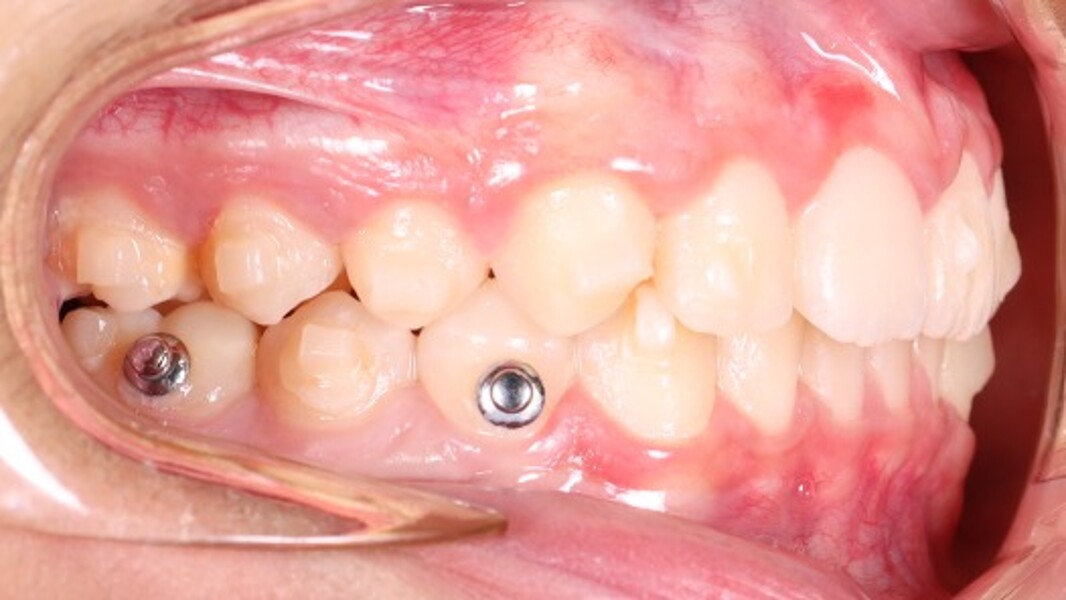

At the end of the first phase of treatment, the clinical findings included (Figs. 5 & 6):

Class I molar and canine relationships on the left side;

half-cusp Class II relationships on the right side;

normal overjet (2.0 mm) and overbite (2.5 mm); and

a posterior open bite, particularly on the left side.

Cephalometric analysis showed that the sagittal discrepancy had been significantly reduced (ANB = 3.7°; Wits = 1.8 mm). Mandibular length remained below normative values.

Figs. 6a–e: Intra-oral photographs after the first phase of treatment.